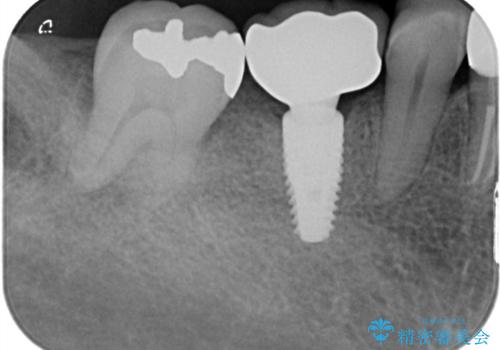

- 定期的に本院に通院されている患者様で、前歯の揺れがあると相談されました。下の奥歯が左右合わせて3本喪失されており、噛み合わせの負担が前歯にも集中していることを説明しました。右下6番の歯に関しては、事前の診査で十分な骨量がありましたのでインプラントを1本埋入しました。左下5番・6番にも本来はインプラントを埋入したかったのですが、骨量が十分でなく、骨を増やす処置をすると神経が近くリスクがあることから、審美性に配慮した金属のばねが見えないノンクラスプデンチャーを製作しました。また、このとき入れ歯を支える左下7番に根尖病変がありましたので、根管治療も行っております。(根管治療は当院院長で専門医を持つDr.林が担当しています。)治療終了後、約1年が経過しましたが、問題なく経過しており患者様も喜ばれていました。